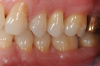

Fig 13. Stability of the soft tissues at 1-year follow-up.

Figure 13

In the present case, the patient's postoperative protocol included the administration of analgesics and mouthrinse. Plaque control and polishing were performed every 2 to 3 weeks for the first 3 months. The patient was then placed on a 3-month recall system. At the 1-year follow-up, stability of the soft and hard tissues could be observed (Figure 13 and Figure 14). Following the seven-key checklist, this clinical case demonstrated that correct case selection, with consideration given to patient-, tooth-, defect-, and operator-related factors, combined with the use of an evidence-based surgical protocol, led to predictable outcomes.